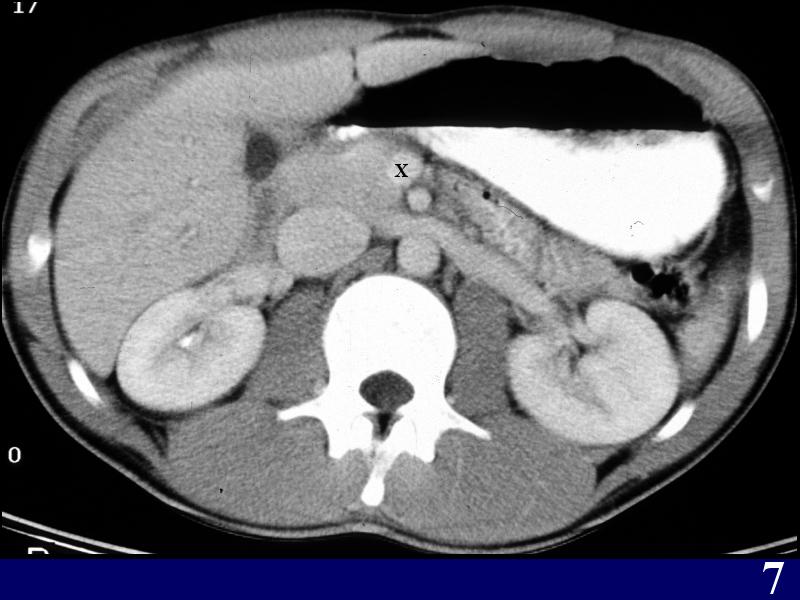

MS 190 CT 18